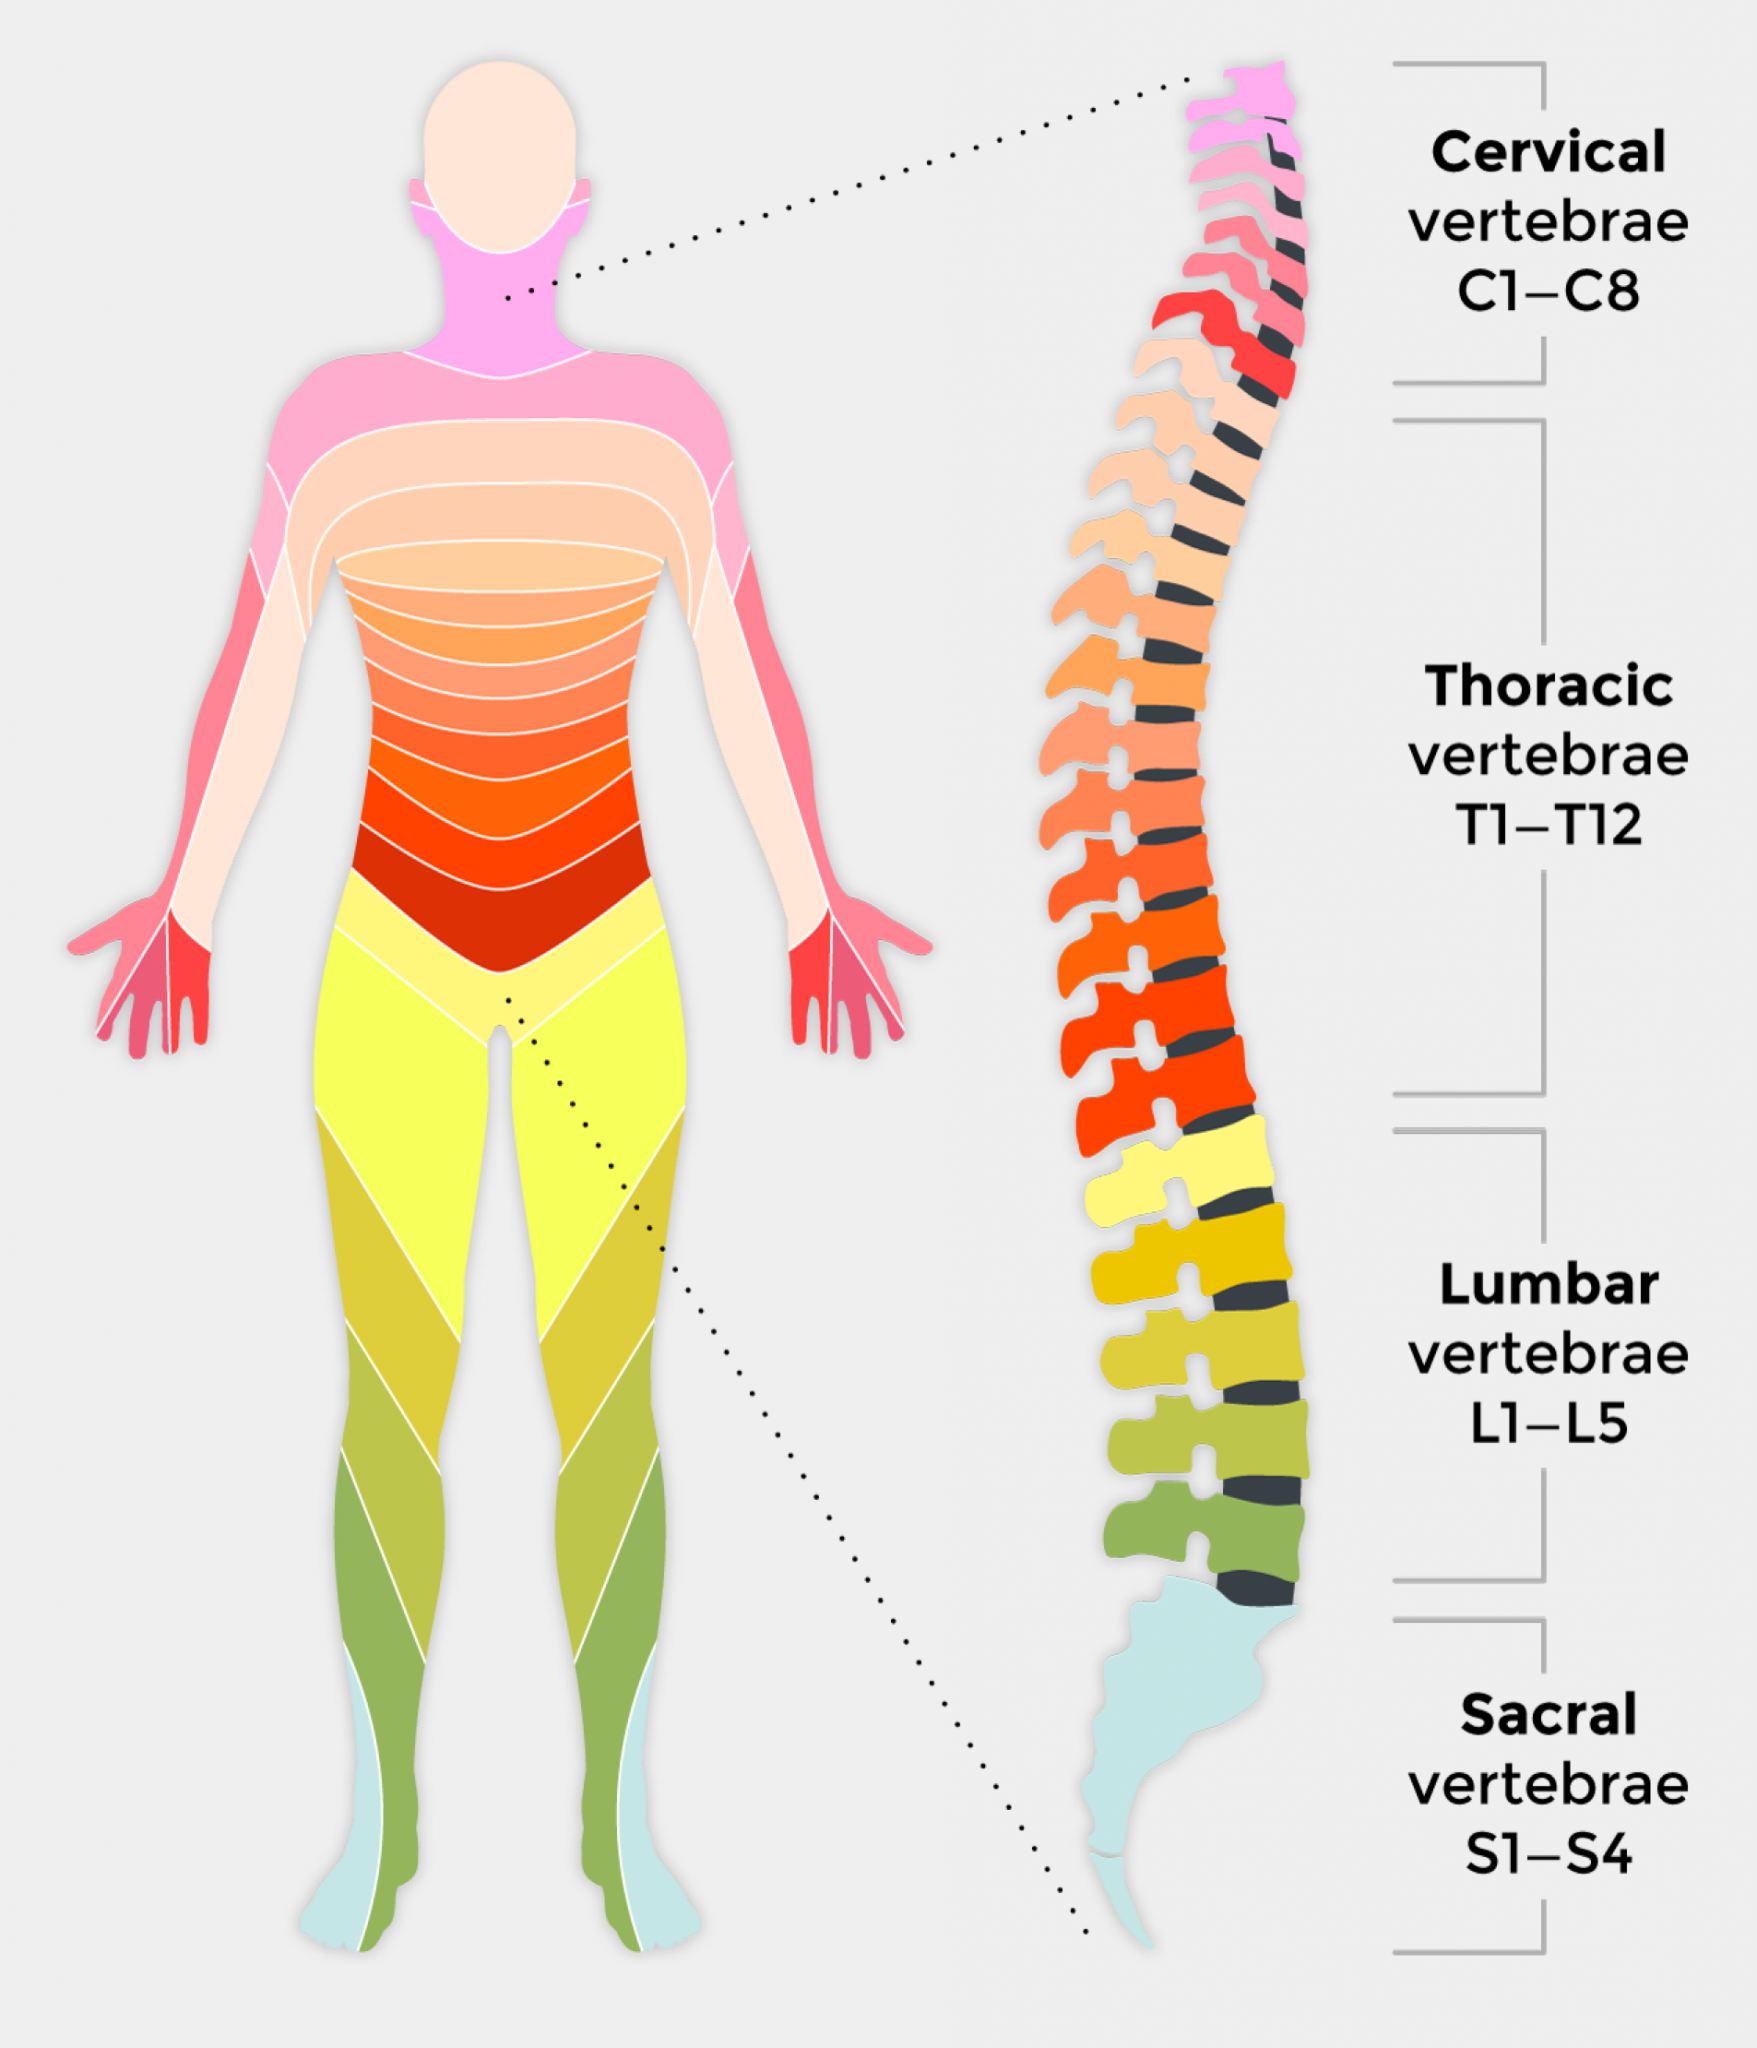

Anatomy of Spinal Cord Injury – Treatment, Complication – Rxharun

Spinal Cord Injury Levels | Bone and Spine | Spinal cord injury, Spinal …

What is a Spinal Cord Injury (SCI)? – First Aid for Free